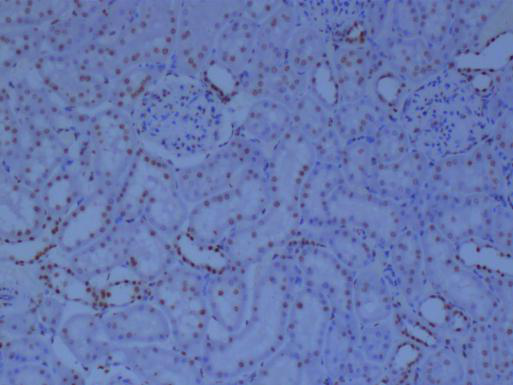

小鼠大腦冰凍切片

→根據顯微鏡下的觀察,鑒別切片中的組織類型和細胞形態。不同的組織類型和細胞形態反映了不同的生理或病理狀態。

→注意觀察細胞的大小、形狀、排列方式以及細胞核和細胞質的特征,這些特征可以提供關于細胞狀態的重要線索。

→觀察細胞是否出現異常增大或縮小,核的大小、形狀、染色深淺等是否正常,以及細胞質的染色情況是否有顆粒感、空泡等異常改變。